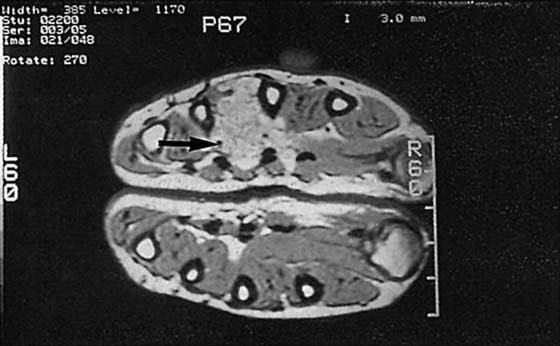

MRI plays a limited role in the examination of patients with possible carpal tunnel disease. By and large, the diagnosis of this problem should be reached clinically, but MRI may be used occasionally if the symptoms derive from a soft tissue mass or an infection within the carpal tunnel.59,60 Indications for wrist MRI include atypical symptoms, a lack of EMG findings, high clinical suspicion for a mass, young patient age (possible congenital anomalies), and recurrent symptoms in postoperative patients.

On MRI, the flexor retinaculum is normally taut to minimally convex, the median nerve is of uniform size (4 × 2 mm) and ovoid in shape with signal isointense to muscle, and the flexor tendons are not distinguishable from one another on T2-weighted sequences. MRI findings of CTS include volar bowing of the flexor retinaculum, synovitis of the tendon sheaths within the carpal tunnel, focal enlargement of the median nerve at the level of the pisiform, and increased signal of the nerve itself. The median nerve may alternatively appear flattened. Note that these findings are nonspecific in the absence of symptoms. High signal within the median nerve is the least reliable sign and is often seen in asymptomatic individuals. Mild bowing of the flexor retinaculum may be physiologic; thus, CTS should not be suggested unless this finding is marked. Masses rarely cause CTS, but the search for masses must be diligent. Ganglion cysts, lipomas extending from the thenar or hypothenar eminences, or focal amyloid deposition may be causative lesions. A dedicated extremity MRI may be a cost-effective way to make this diagnosis.